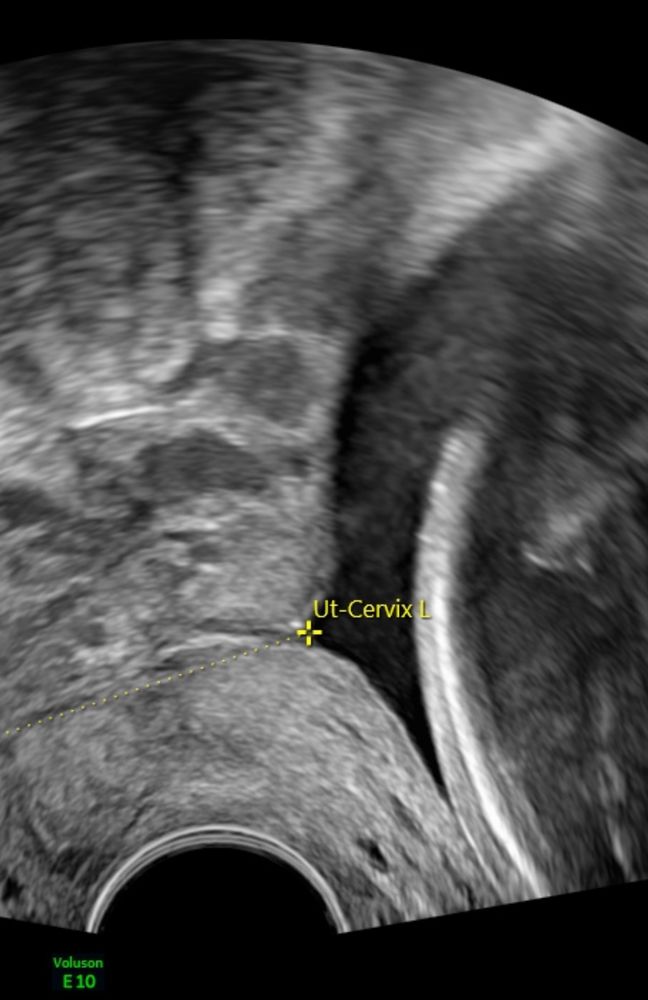

Шейка V образное расширение до 5,5мм

и V образное расширение до 5,5 мм. зев закрыт.